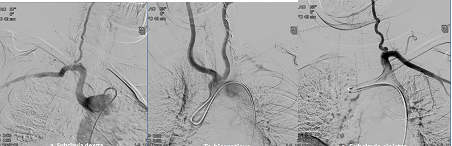

В послеоперационном периоде больная была дополнительно обследована: выполнена компьютерная томография шеи и органов грудной клетки с ангиографией (рис. 3 а, б) и прямая ангиография (рис. 4), по данным которых подтверждено наличие у пациентки аномалии развития ветвей аорты. Правая подключичная артерия отходит от уровня перешейка аорты по ее задней поверхности самостоятельным стволом, проходя между аортой и позвоночным столбом на уровне третьего позвонка, – a. lusoria. От правой подключичной артерии отходит правая позвоночная артерия. Правая общая сонная артерия отходила от аорты одним устьем вместе с левой общей сонной артерией, что наглядно демонстрируется на ангиограммах в виде симптома “бычьих рогов”. Послеоперационный период у больной протекал гладко, без осложнений. Фонация голосовых связок не была изменена.

Рис. 4. Ангиография (селективное контрастирование сонных, левой и правой подключичных артерий).

По данным ангиографии – ангиографическая картина a. lusoria. Справа налево от дуги аорты отходят устья правой и левой общих сонных артерий, левой подключичной артерии и правой подключичной артерии (последние два практически на одном уровне) (рис. 7).